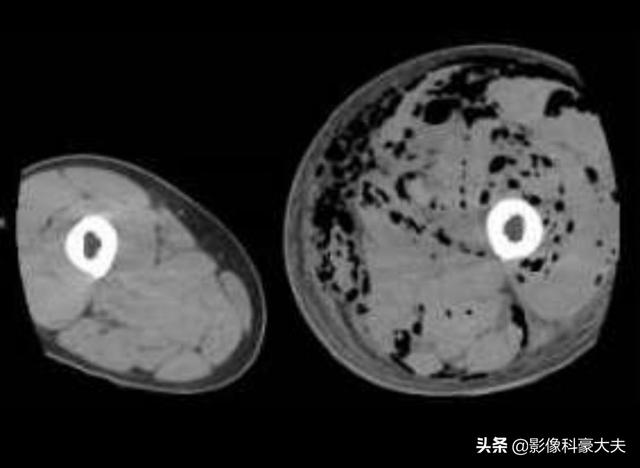

下の写真は、32歳で血糖値が30台だった患者がクレブシエラ菌に感染し、肺膿瘍、肝膿瘍、下肢感染症を引き起こしたものである:

左足は目に見えて腫れており、筋肉の隙間に黒い泡がたくさんある。このような重症感染症の患者は死亡率が高い!